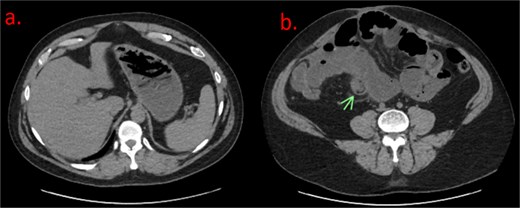

Labs were significant for leukocytosis to 13.4 and an isolated elevated alkaline phosphatase of 142. All other chemistries were stable. Initial read of non-contrast computed tomography (CT) abdomen/pelvis showed likely SBO with dilated loops of small bowel (Fig. 1). Image A shows a fluid-filled stomach. In image B, there is a “bowel-within-bowel” appearance concerning for intussusception as a lead point for SBO.

(a) Axial noncontrast CT of the abdomen demonstrating a nondescript, fluid-filled stomach. (b) Axial noncontrast CT reveals dilated loops of small bowel with classic “bowel within bowel” appearance of the small intestine, labeled with an arrow. This was thought to be the lead point for the suspected SBO.